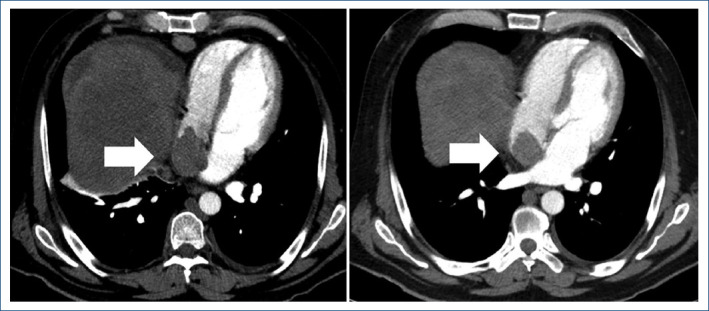

肝细胞癌伴下腔静脉肿瘤血栓延伸至心室1例。

Hepatocellular carcinoma with inferior vena cava tumor thrombus extending into cardiac chambers: case report.